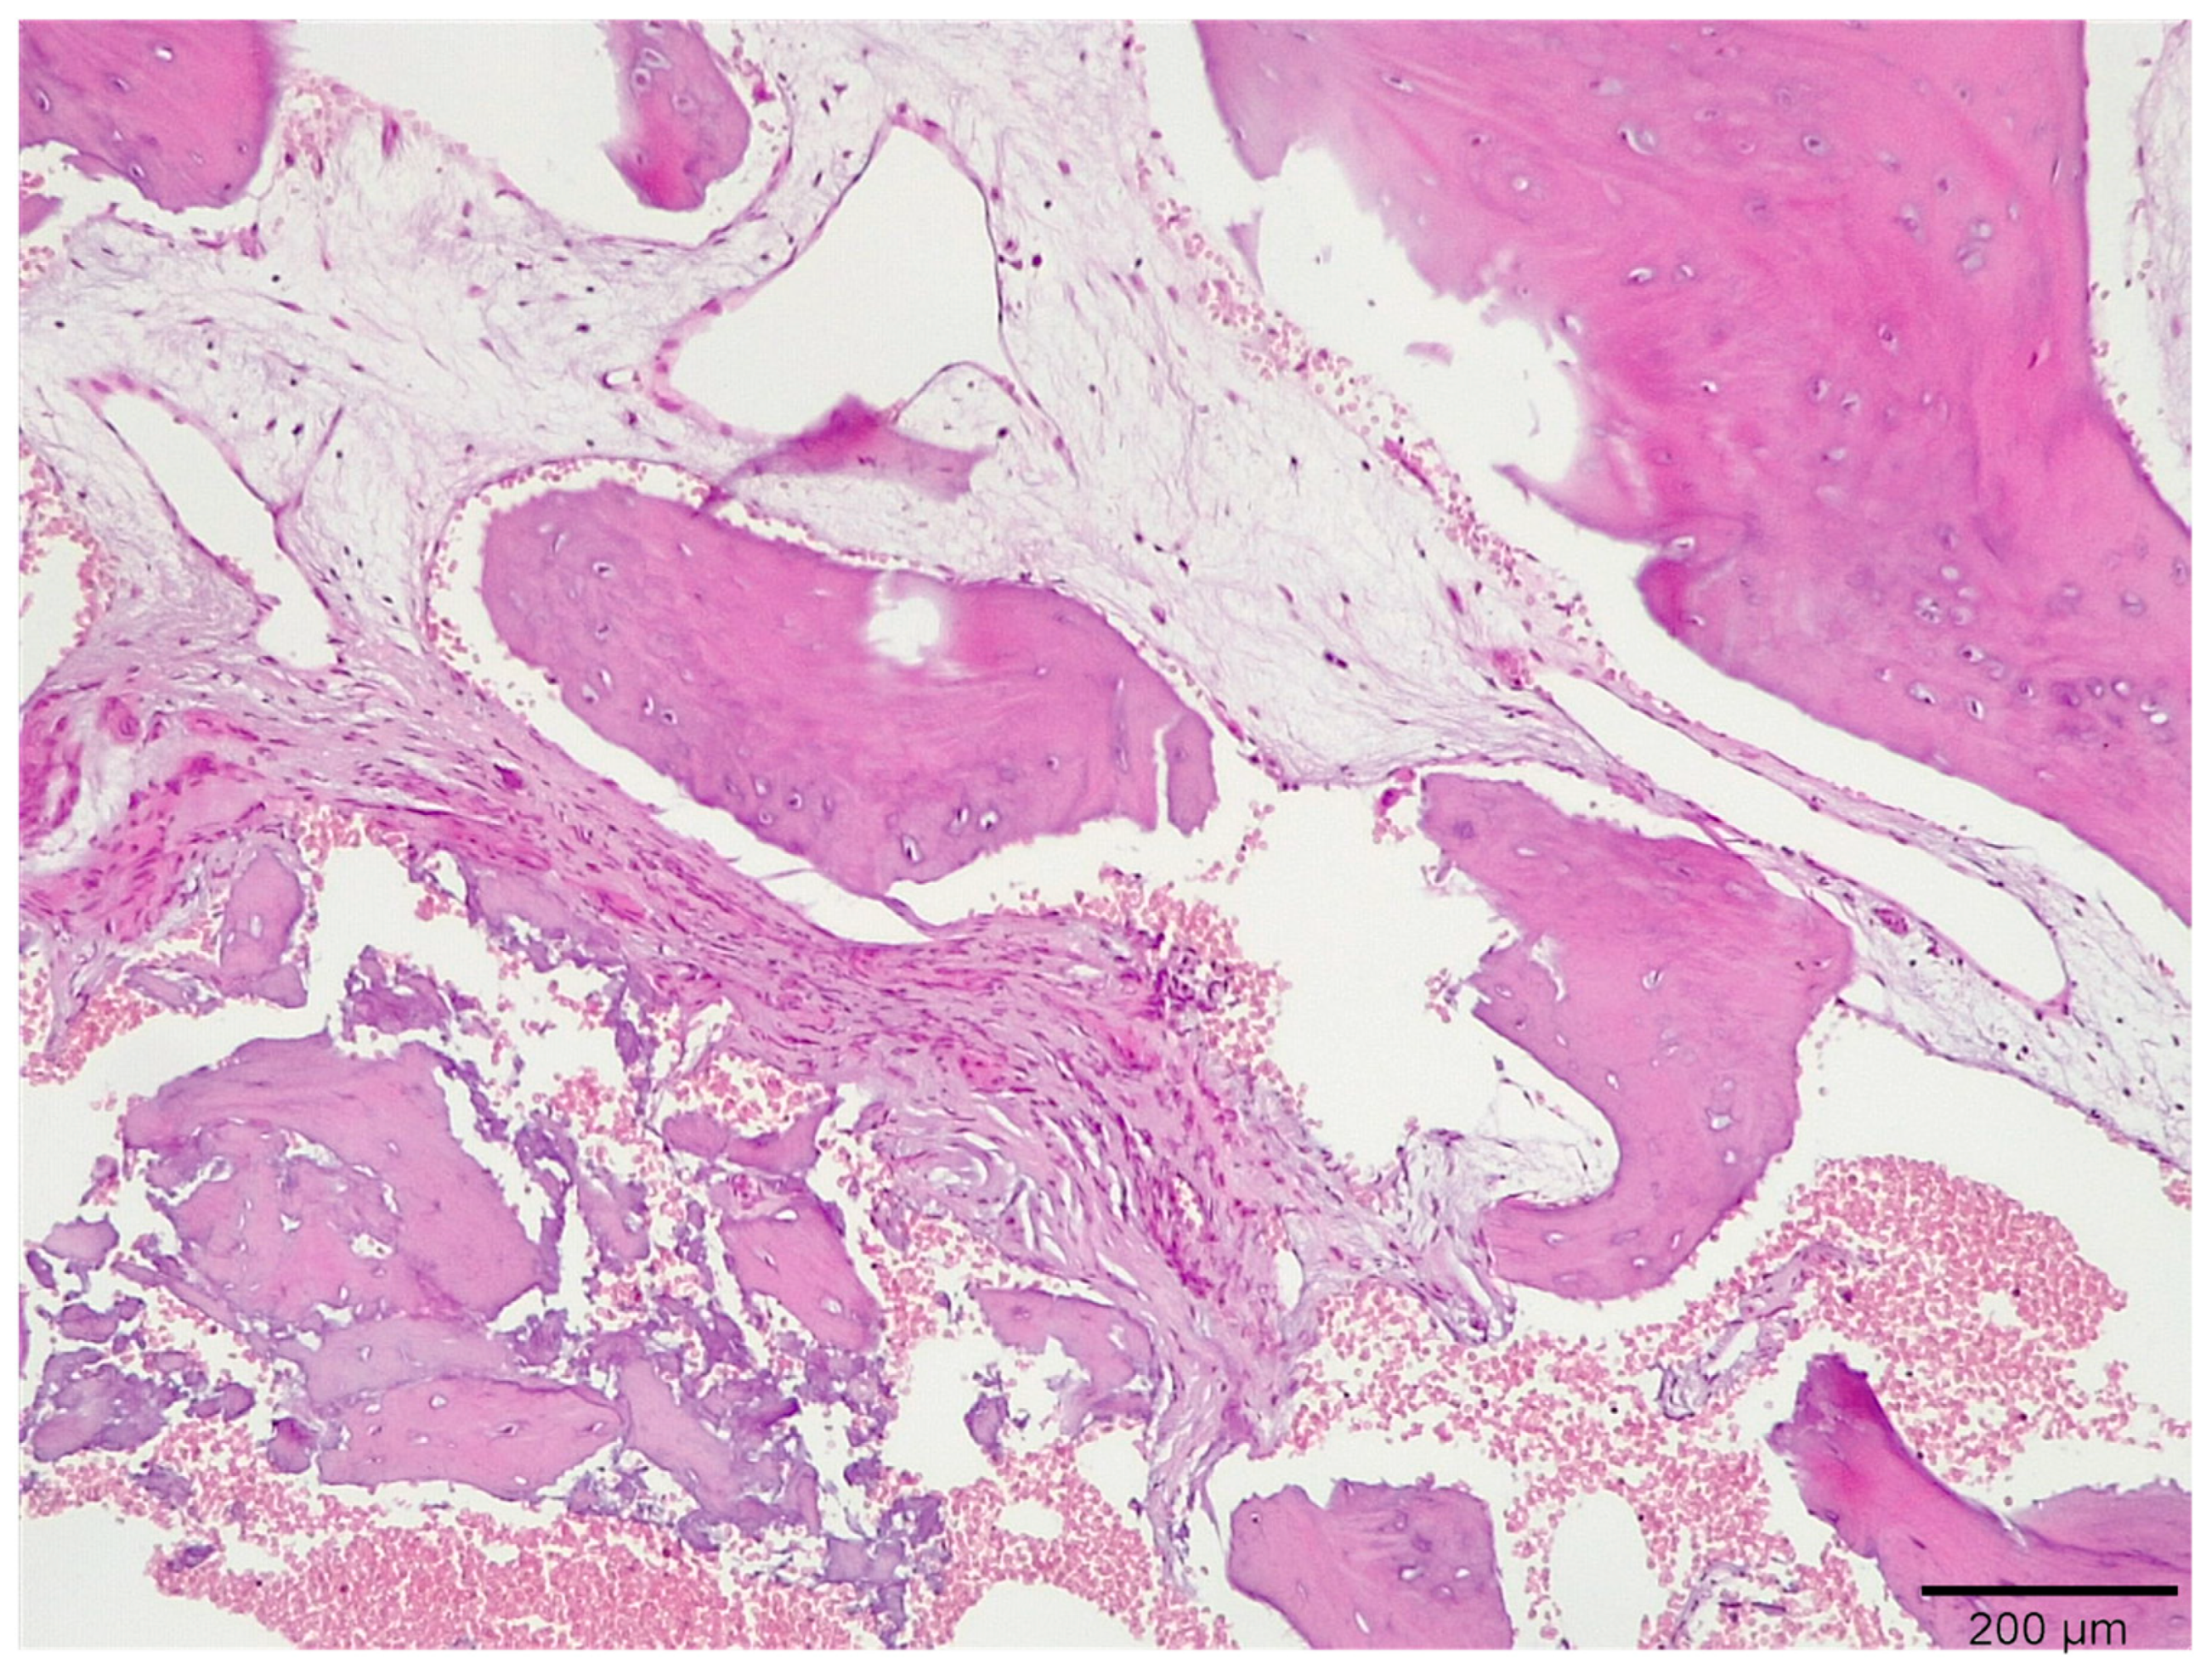

3.1. Histological Analysis Showed Signs of New Bone Formation at 60 Days

3.2. Histologic Data Obtained after Samples Analysis at 24 Months of Evaluation